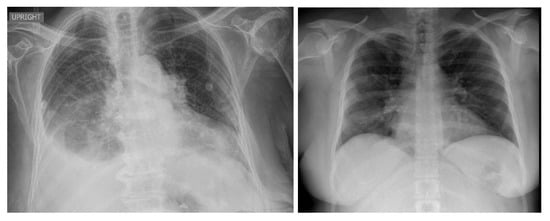

5. Model Explainability